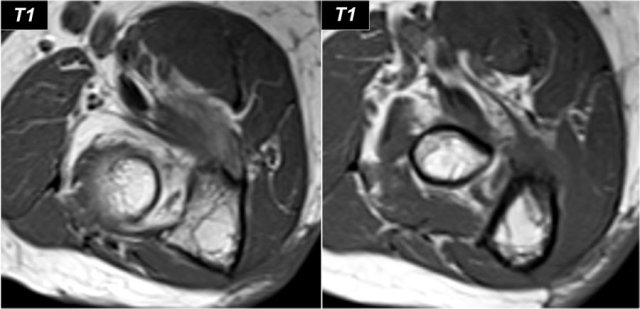

In this case there is chronic atrophy with high sinal on T1, which is irreversible.

In early or subacute denervation the prominent sign is edema with high signal on T2W-images and that is reversible.

This is a 48 year old male with Marfan's syndrome, who had a sudden onset of right hand weakness.

This is a nice example of subacute denervation.

Notice on the T1W-image that there is no atrophy.

Only edema on the T2W-image.

This was due to proximal radial neuropathy.